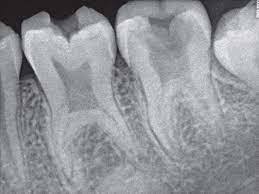

what does this radiograph show an image of ?

taurodotism

elongated pulp chamber and short roots